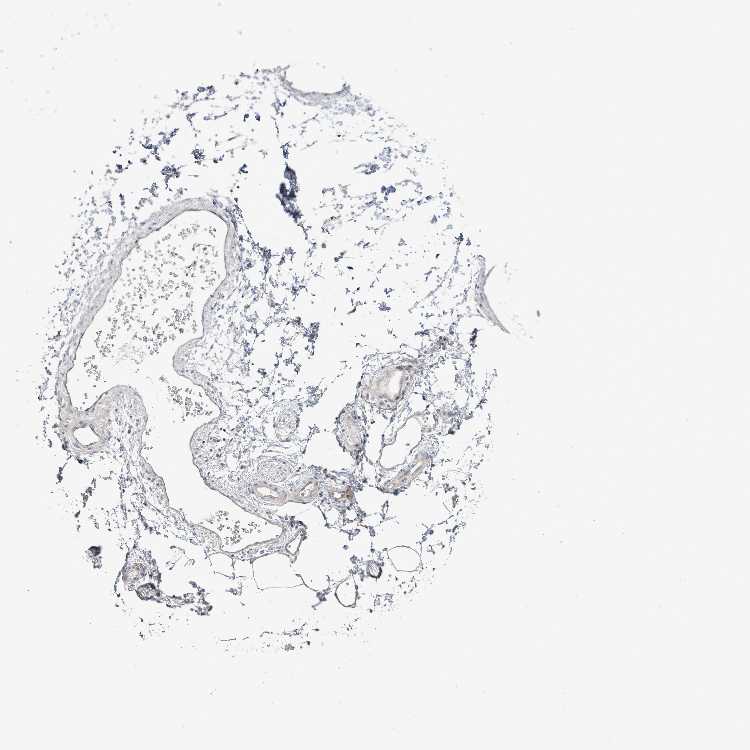

SOFT TISSUE 2 - Antibody stainingi

Antibody staining in the annotated cell types in the current human tissue is reported as not detected, low, medium, or high, based on conventional immunohistochemistry profiling in selected tissues. This score is based on the combination of the staining intensity and fraction of stained cells.

Each image is clickable and will lead to virtual microscopy that enables deeper exploration of all samples and also displays staining intensity scores, fraction scores and subcellular localization as well as patient and tissue information for each sample.

Antibody HPA049418

Fibroblasts Not detected

Peripheral nerve Not detected